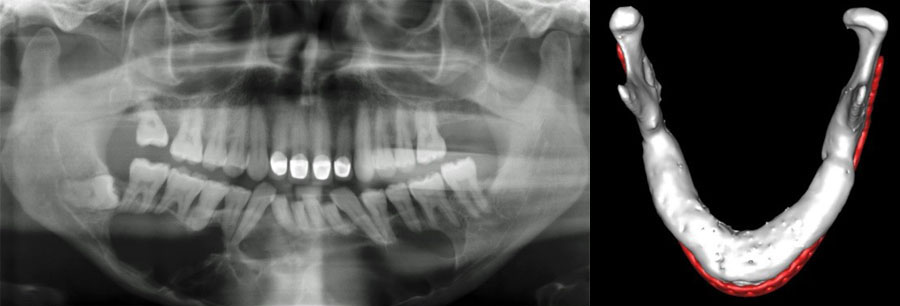

In contrast the particulate, compressed, autologous bone graft overcomes many of these challenges. Due to its mouldable properties it adapts to an arch and allows for the superior restitution of mandibular arch form and alveolar height (Figure 1), whilst significantly reducing patient morbidity and treatment costs.